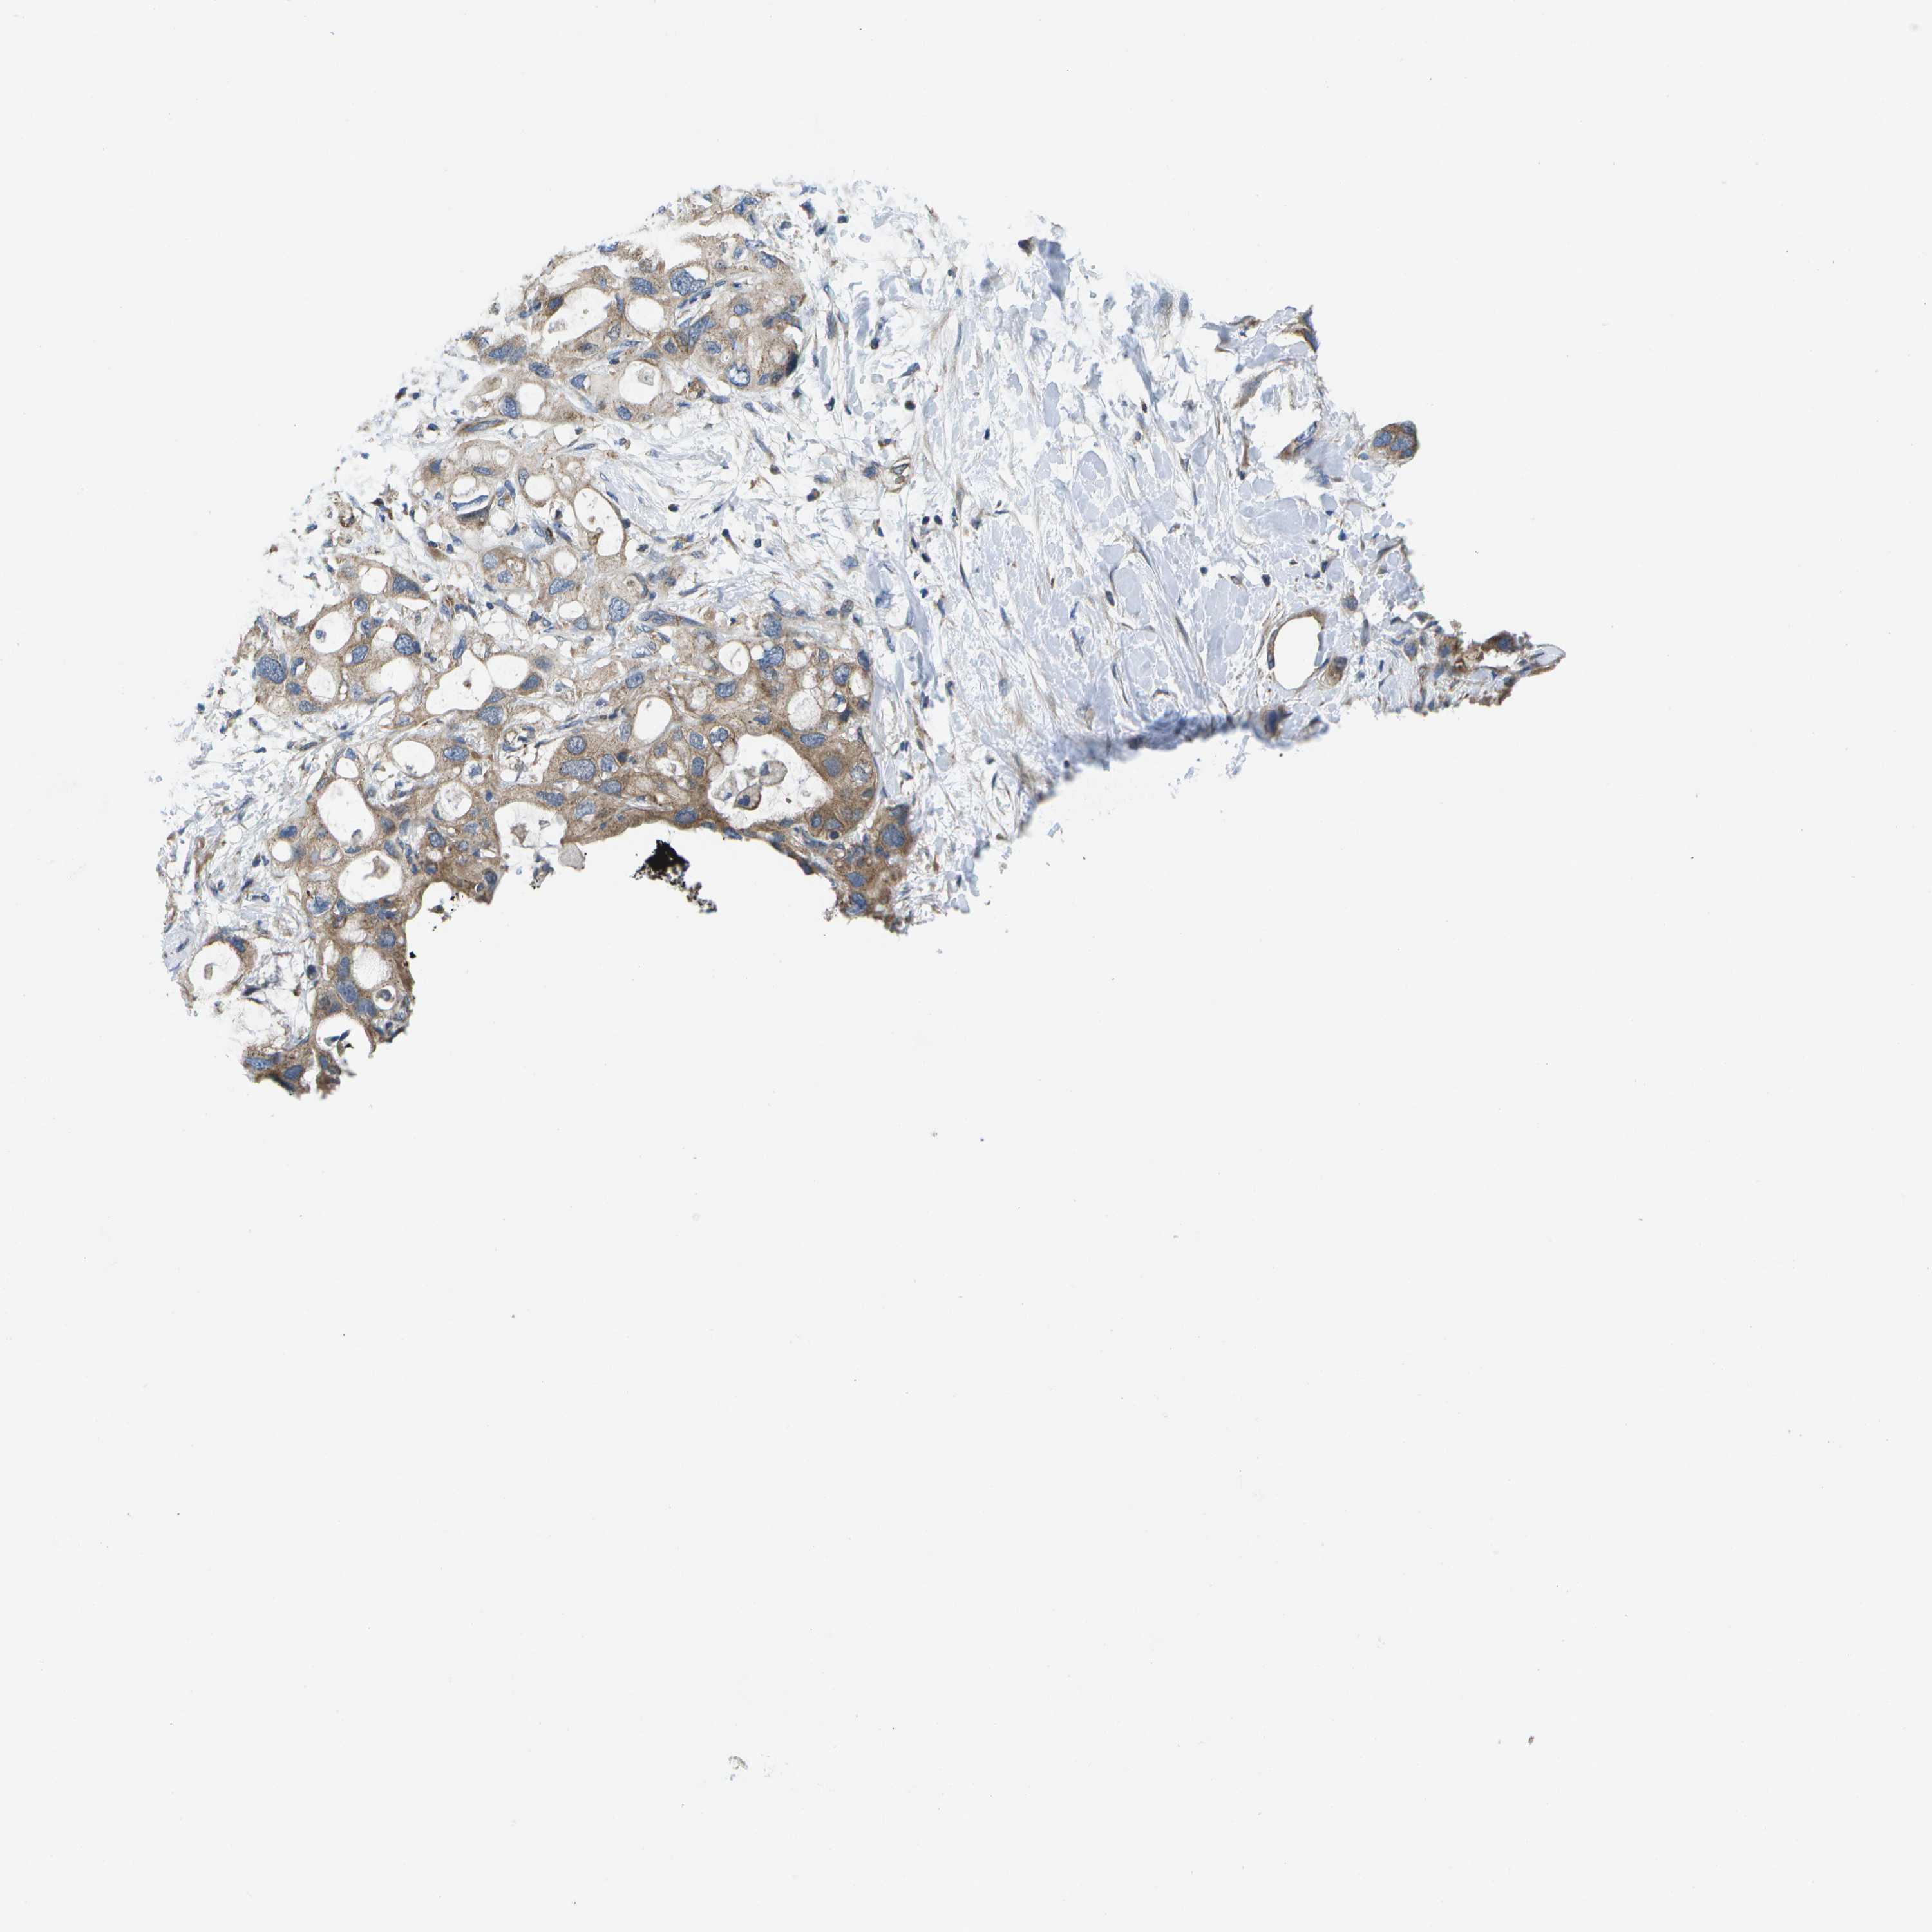

PANCREATIC CANCER - Protein expressioni

A mouse-over function shows sample information and annotation data. Click on an image to view it in a full screen mode. Samples can be filtered based on level of antibody staining by selecting one or several of the following categories: high, medium, low and not detected. The assay and annotation is described here.

Note that samples used for immunohistochemistry by the Human Protein Atlas do not correspond to samples in the TCGA dataset.

Antibody stainingi

Antibody staining in the annotated cell types in the current human tissue is reported as not detected, low, medium, or high, based on conventional immunohistochemistry profiling in selected tissues. This score is based on the combination of the staining intensity and fraction of stained cells.

Each image is clickable and will lead to virtual microscopy that enables deeper exploration of all samples and also displays staining intensity scores, fraction scores and subcellular localization as well as patient and tissue information for each sample.

Antibody HPA016961

Staining

High

Medium

Low

Not detected

Intensity

Strong

Moderate

Weak

Negative

Quantity

>75%

75%-25%

<25%

None

Location

Nuclear

Cytoplasmic/membranous

Cytoplasmic/membranous,nuclear

Adenocarcinoma, NOS